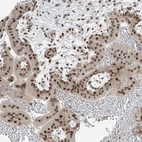

Immunohistochemical staining of human placenta shows strong nuclear positivity in trophoblastic cells.